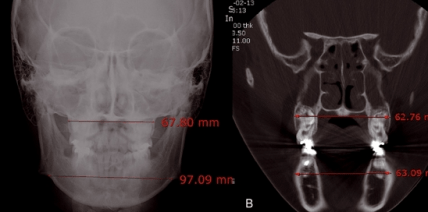

• Er ist der Erfinder der MARPE (Miniscrew Assisted Palatal Expansion).